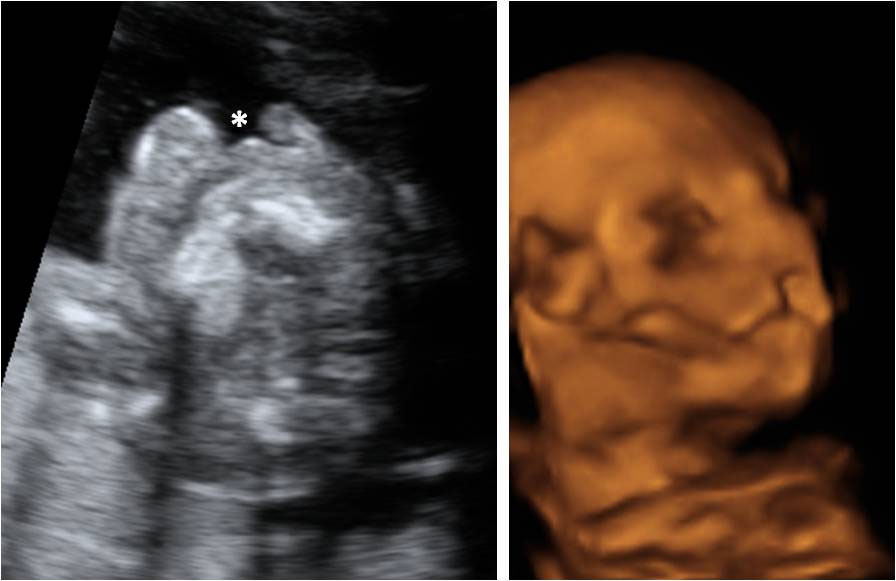

Cara de un bebé de 18 semanas

En la ecografía en 4D de un feto de 18 semanas de embarazo se ve la cara ya armonizada: las orejas y los ojos que en un principio estaban desplazados, ya se encuentran en su lugar, lo que le da una imagen mucho más "humana". Ecografía de la cara de un bebé de 18 semanas A esta edad...